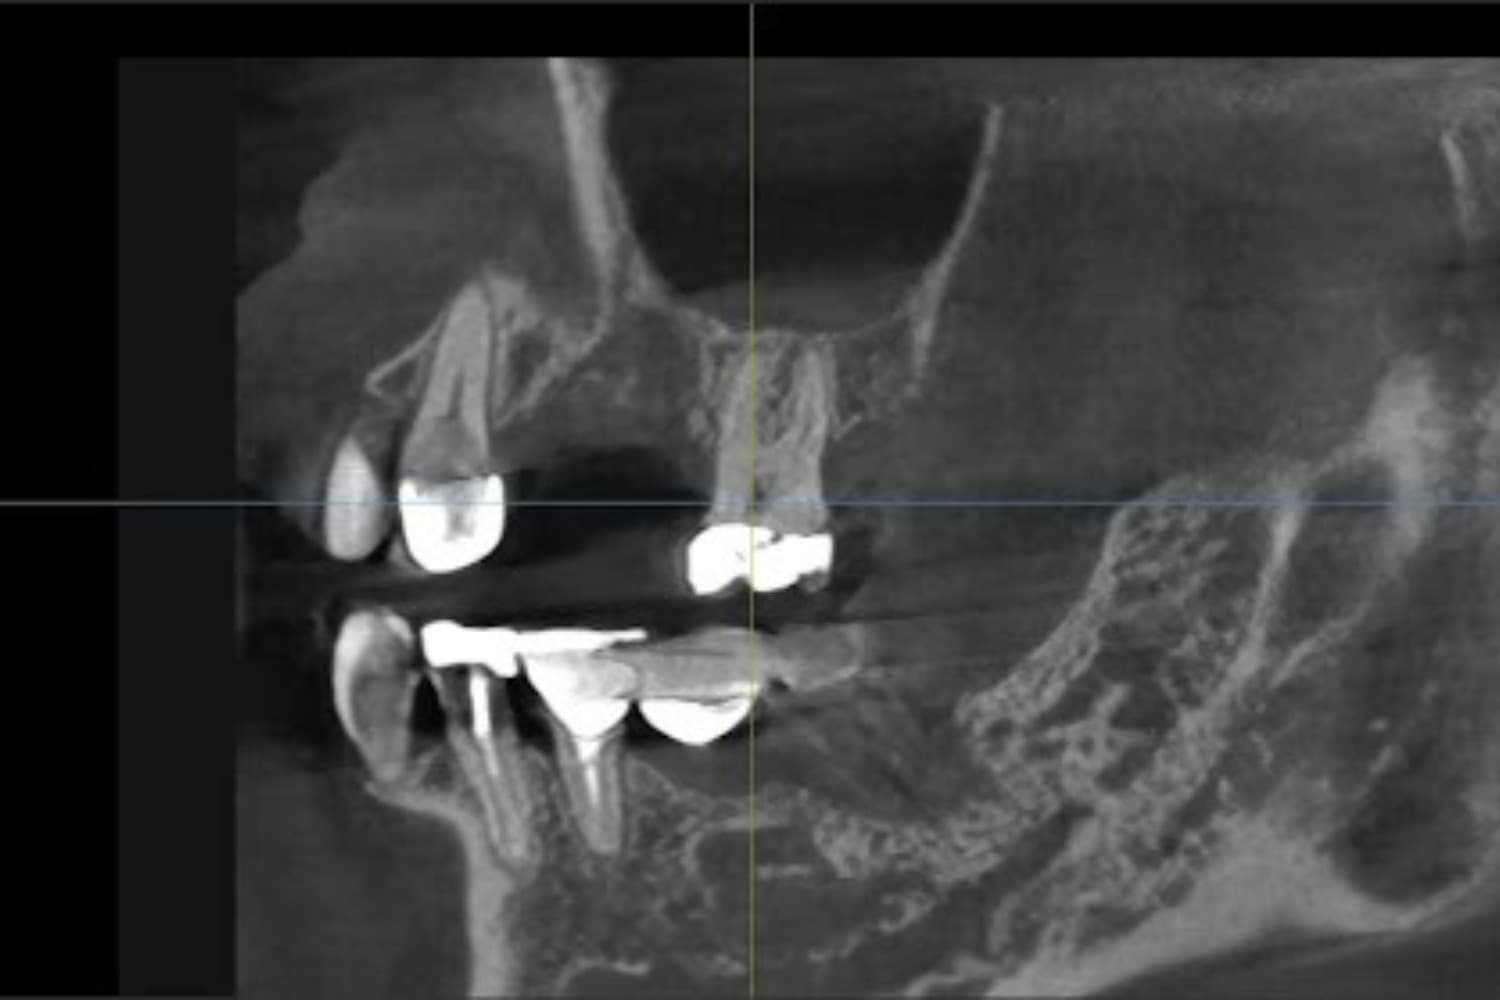

Short (短期間治療) 枚方市のインプラント治療 従来のインプラント治療では抜歯後3~6か月の期間を置くケースが少なくありませんが、当院では抜歯直後または抜歯後早期にインプラントを埋め込む手術を行っています。条件がそろえば、その日のうちに仮歯を入れることも可能です。 また当院ではEXOCADと呼ばれるCADソフトを導入しているため、上部構造(最終的な被せ物)を短期間で製作しやすい点も特徴です。 通常は噛めるようになるまで半年~1年程度かかるところ、当院なら抜歯後最短2か月程度、4~5回の通院で噛む力を回復できます。 Simple (シンプル) 枚方市のインプラント治療 インプラントを埋め込む部分の骨が少ない場合、これまではインプラント手術を行う前に、別途「GBR」「サイナスリフト」といった骨を作るための外科手術をしなくてはなりませんでした。 手術の機会が増えると、それだけ患者さまのお体や、時間・金銭面などのご負担が増えてしまうのは言うまでもありません。 当院なら抜歯直後や抜歯後早期にインプラント手術を行えます。このことにより、従来の大掛かりな骨造成術(GBR)を行わずに、インプラント手術をおこなうことが可能となりました。また、上顎の臼歯部に骨がない場合、従来のサイナスリフトでは、上顎洞に人工骨を入れ、その後、インプラントを埋入するという複雑な治療が必要でしたが、「エキストラショートワイドインプラント」と特殊な器具を使用することで、一回のインプラントの手術で終わらせることも可能となりました。 当院では追加の外科処置を不要にし、患者さまのご負担を減らしながら極めてシンプルなインプラント治療を行っています。 Small (最小限) 枚方市のインプラント治療 前述の通り、当院では追加の外科処置が必要ありません。さらに、従来よりも短めのインプラントを使用しています。そのため手術によるお体への影響が少なく、体に優しいインプラント治療を受けていただけます。 最小限の治療で、しっかりと噛めるお口を取り戻せるインプラント治療をご提供しているのが特徴です。 Safe(安全) 枚方市のインプラント治療 サージカルガイド インプラントを埋め込むあごの骨の中には、重要な神経や血管がたくさん通っています。それらを傷つけずに手術を完了させるには、事前の精密検査および診査診断が重要です。 当院では事前に必ず歯科用CTによる撮影を実施し、3次元的にあごの骨の状態を確認しています。これを元に、どのような角度でインプラントを埋め込むべきかシミュレーションを行います。 手術中の安全性をより一層高め、インプラントを正しく埋め込むために使うのが「サージカルガイド」と呼ばれる器具です。このガイドを作製することで、シミュレーション通りの角度・位置に埋め込めるよう注力しています。 また、専用のソフトを使ってインプラント治療後のお口の将来像も作成しています。患者さまにもご覧いただきますので、治療のイメージを掴みやすいのではないでしょうか。 衛生面でも、手術中に使用する器具はすべて個包装にし、高圧蒸気滅菌を実施。使用直前まで開封しませんので、清潔な器具で治療を行えます。こうしたさまざまな取り組みにより、安心・安全に治療を受けていただけるよう努めています。

親知らずの抜歯やインプラント治療で精密な診査診断ができるよう、通常のレントゲンに加えて歯科用CTを導入しています。 治療前には診査診断に加え、患者さまとしっかりお話をしてご不安やご要望を伺います。その上で、治療の理解を深めていただけるようアニメーションなどを用いて丁寧にご説明。治療前後には歯の写真を撮影し、患者さまご自身に仕上がりの確認をお願いしております。

左上の歯のインプラント治療(60代女性)

インプラント抜歯即時埋入・即時荷重(抜歯と同時にインプラントを埋入し、当日に仮歯を入れる)

重度の歯の動揺があり、何もしていなくとも痛みがある。治療にあたって前歯がないことを気にする。